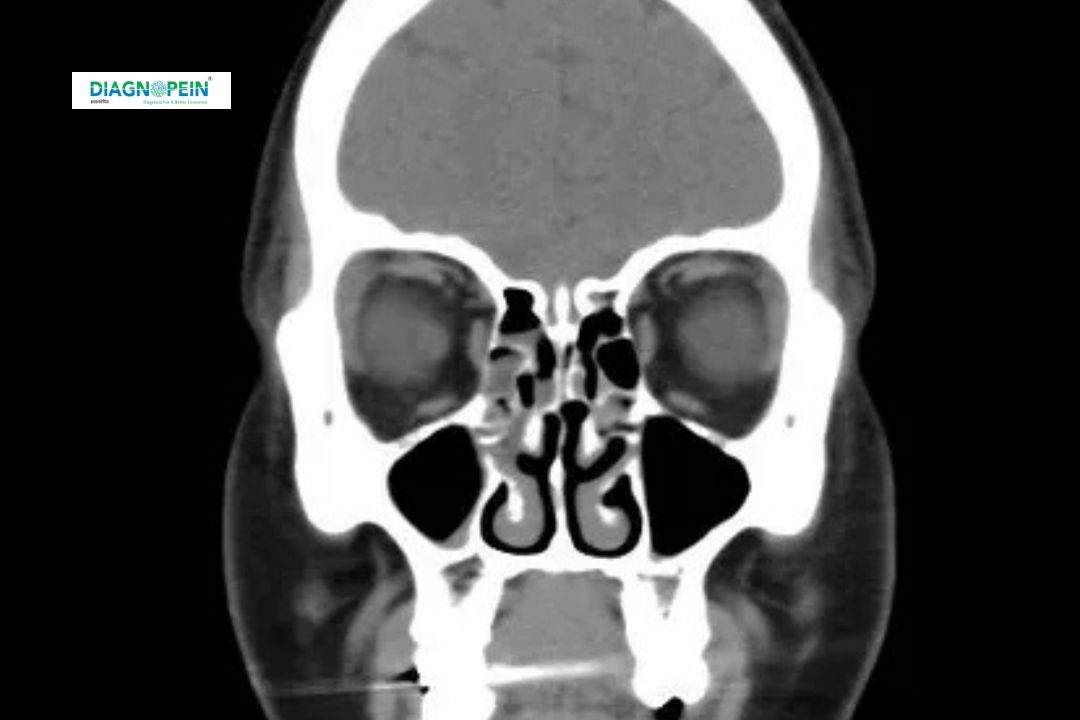

A CT Scan of the orbits with contrast is an advanced imaging test used to examine the eye sockets, surrounding bones, and soft tissues in fine detail. The “contrast” part refers to a special dye injected into the bloodstream to highlight blood vessels, muscles, and possible abnormalities within the orbital region.

CT Orbit With Contrast is a specialized diagnostic scan that combines X-ray imaging with computer processing to produce cross-sectional images of the eye region. Unlike a non-contrast scan, the use of contrast material allows for clearer differentiation between normal tissues and pathological changes.

This scan is often prescribed by doctors to evaluate orbital trauma, eye protrusion (proptosis), vision loss, or suspected tumors. It plays a vital role in differentiating inflammatory lesions from neoplastic ones and helps in understanding the blood supply to the affected area.

CT scans of the orbits are done using thin-slice parameters (0.5–1 mm) for maximum detail. The scan covers:

1. Eye sockets (orbits)

2. Optic nerve and optic canal

3. Extraocular muscles

4. Lacrimal glands and adjoining sinuses